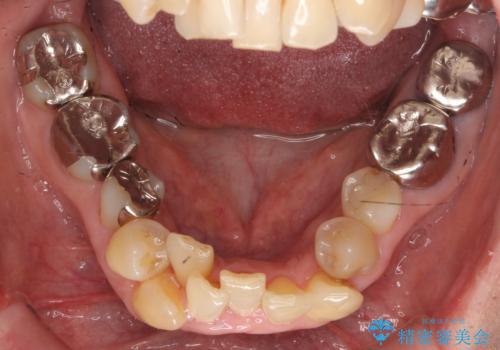

50代女性 八重歯を矯正治療 歯並びの中等度のがたつき

- ワイヤー矯正

- 八重歯の矯正を希望されて来院。

歯は入りきらないため、通常の抜歯矯正を行いました。

歯がご年齢的に動きにくいため、被せ物のやり替えを含めて治療期間の短縮を図りました。

矯正治療自体は2年半、虫歯治療等で1年ほどかかっています。

詰め物や被せ物のやり替えも併せて行っているため、治療期間を比較的短縮できました。